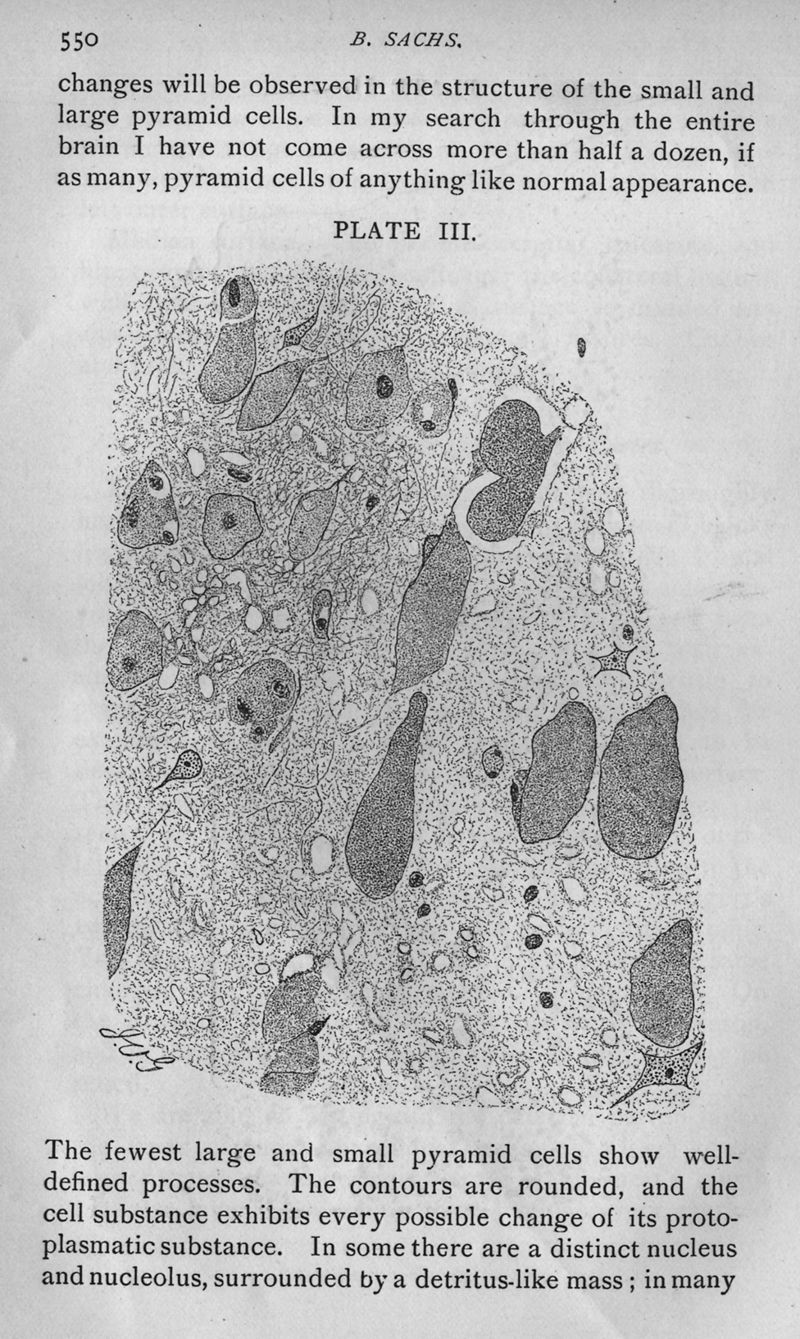

On arrested cerebral development, with special reference to its cortical pathology

In : [The] Journal of nervous and mental disease, 1887, Vol. 14, pp. 541-53